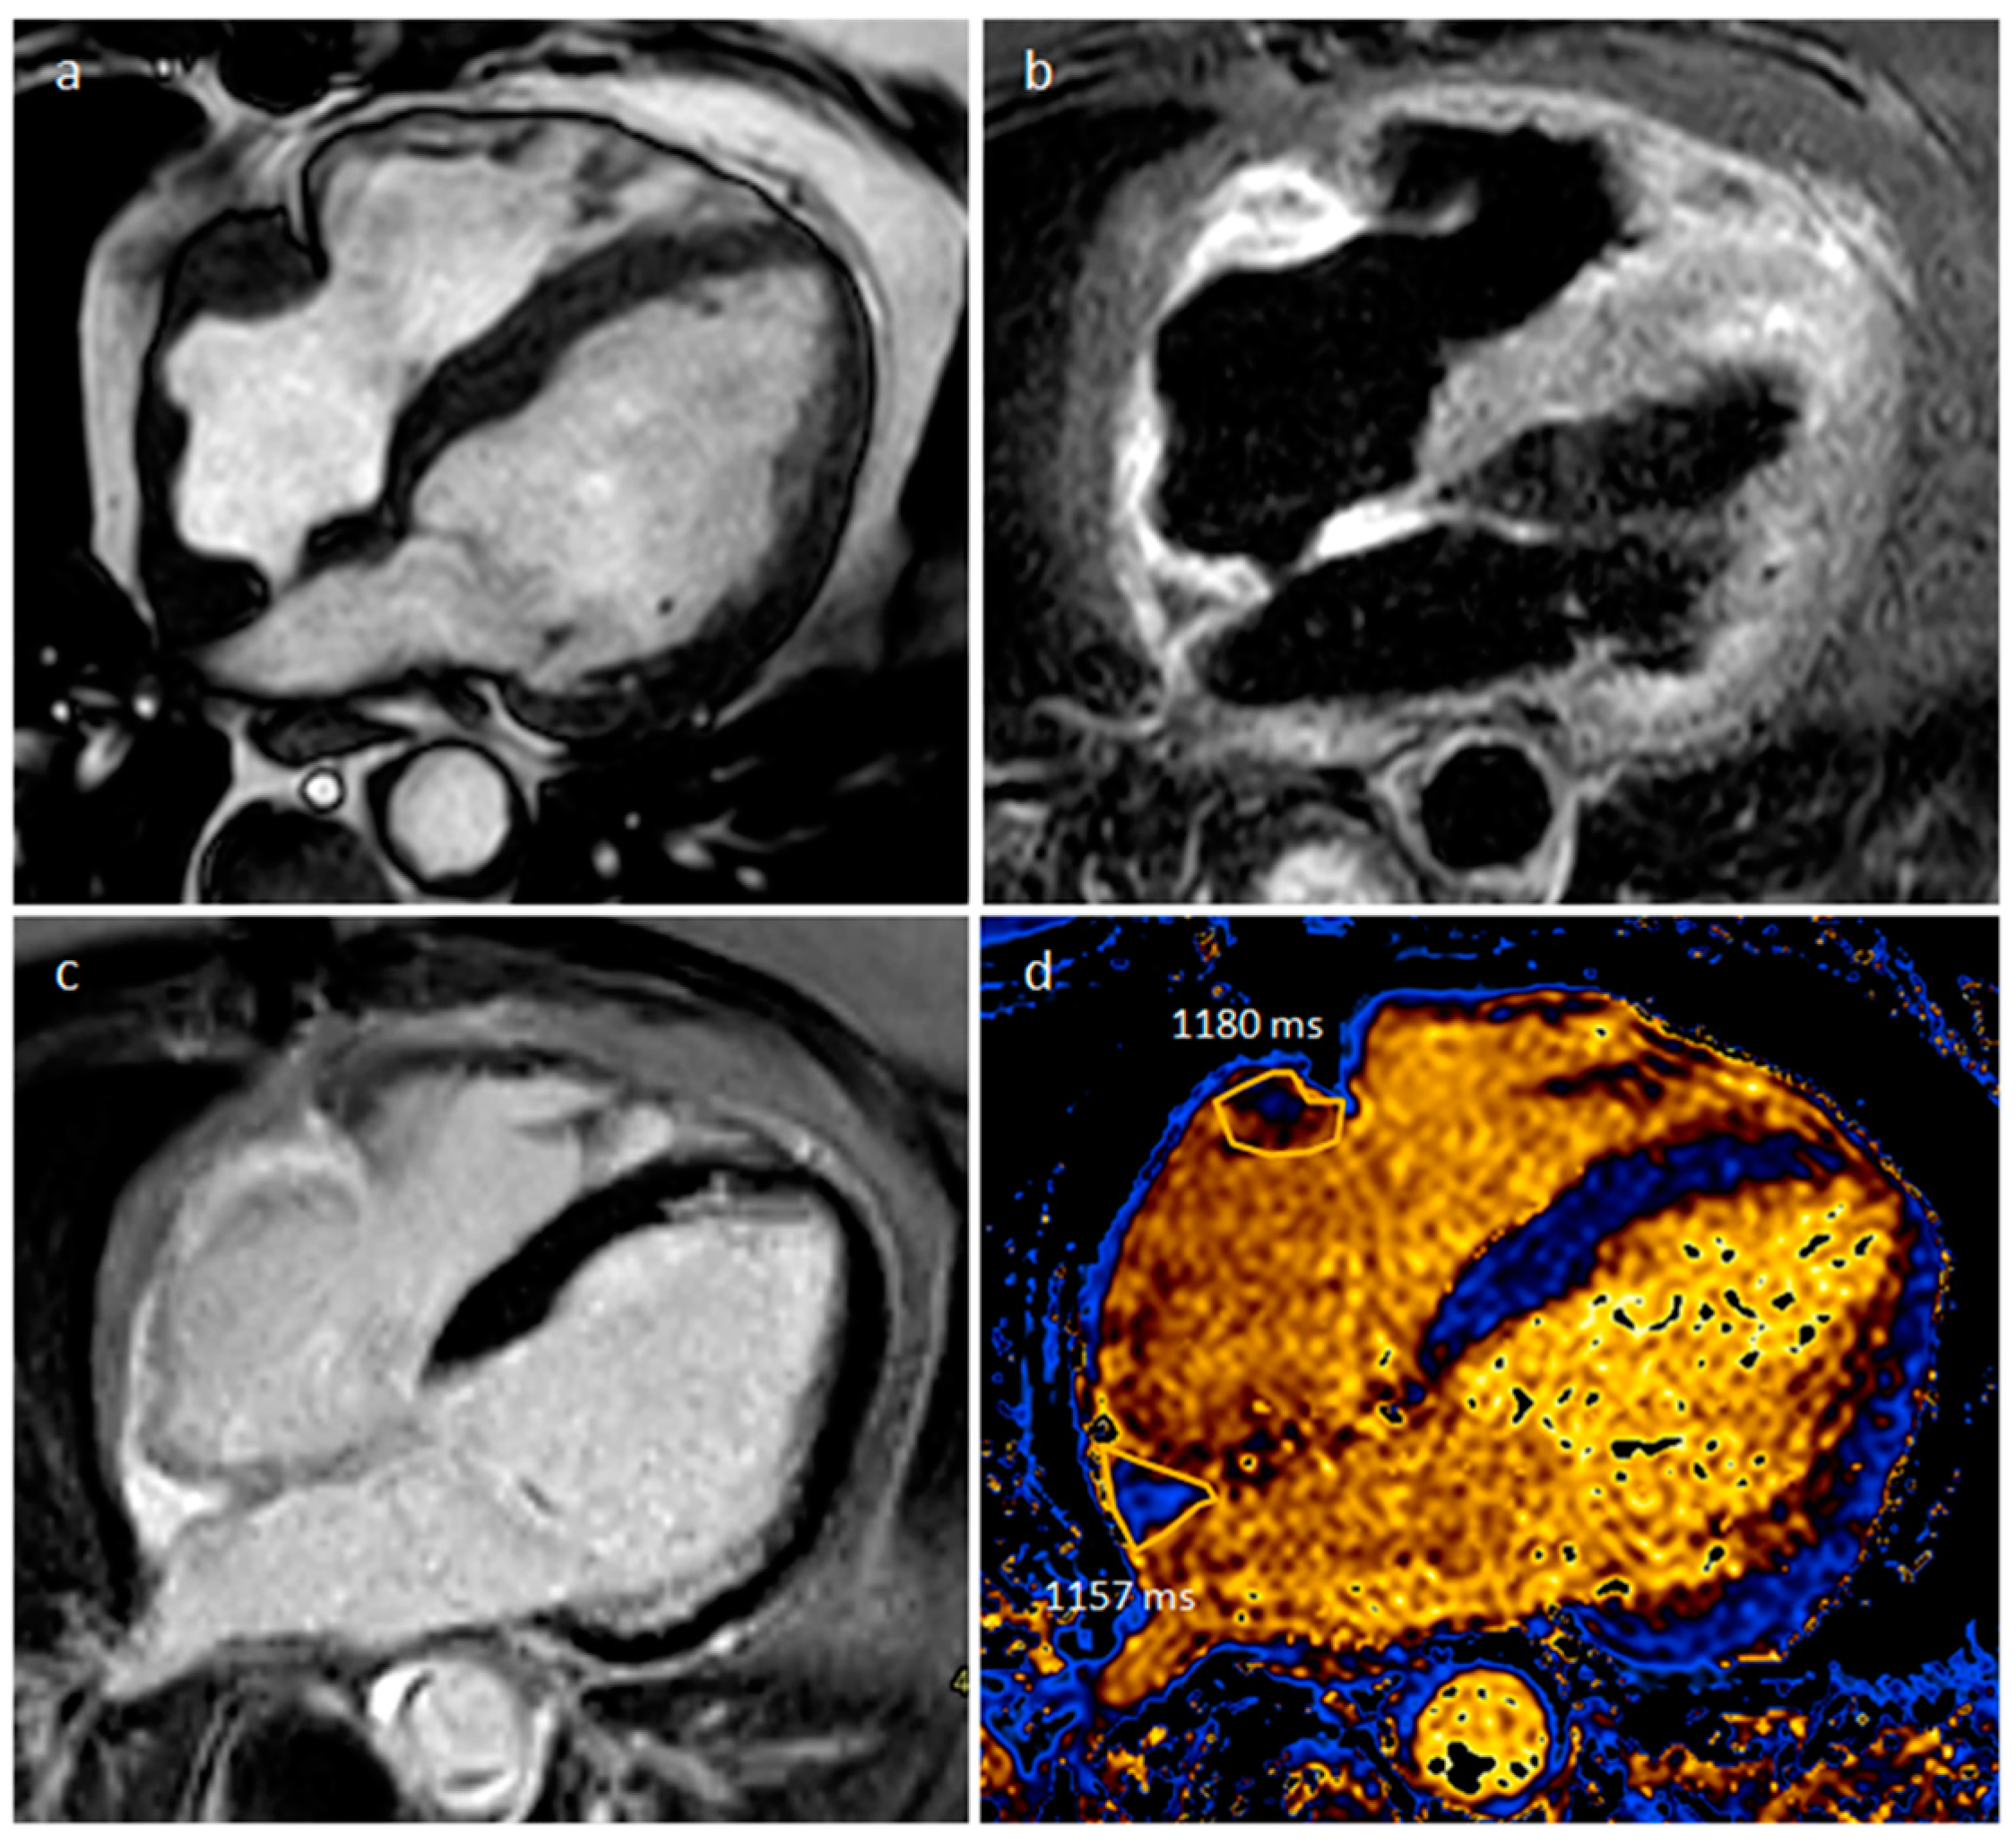

5.3. Primary Cardiac Lymphoma

| Lymphoma | Adulthood, Immunocompromised | RA, RV, pericardium | Pericardial effusion, flow obstruction/heart failure | Uniform, infiltrative, extend along the epicardial surfaces of the heart, encase adjacent vascular structures, hypermetabolic on PET | Pericardial effusion. Tumor might be detected with homogeneous echogenicity. | Pericardial effusion. Normal to low attenuation, heterogeneous and mild contrast enhancement | Iso-hypo T1w, Iso-hyper T2w, none-minimal homogeneous LGE. Evident diffusion restriction |